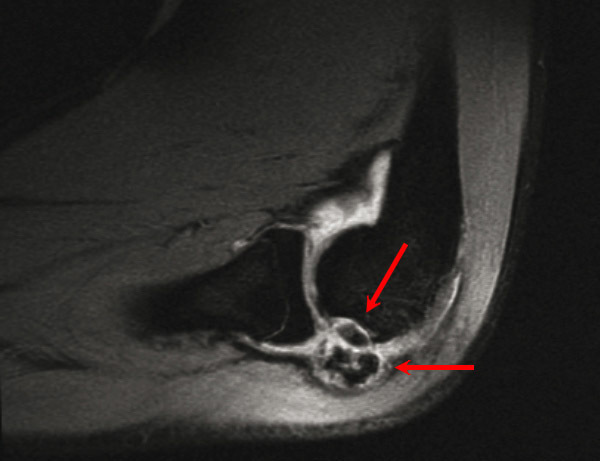

Ostéochondrose articulaire du coude associant un fragment du condyle latéral en place, ainsi que des corps étrangers dans la synoviale articulaire. Voir : P. Journeau, E. Polirzstok, F. Launay, D. Barbier. Lésions osseuses de sollicitation excessive chez l’enfant sportif. Rev Prat 2015;65(8);1084-90.